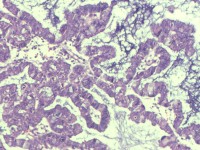

性别

女

年龄

55岁

临床诊断

异常子宫出血

一般病史

阴道不规则出血1月

标本名称

子宫内膜

大体所见

灰白色组织1堆、4*3.4*2.2CM大。

能诊断癌吗

图4

子宫内膜样腺癌

雾蒙蒙:

支持。